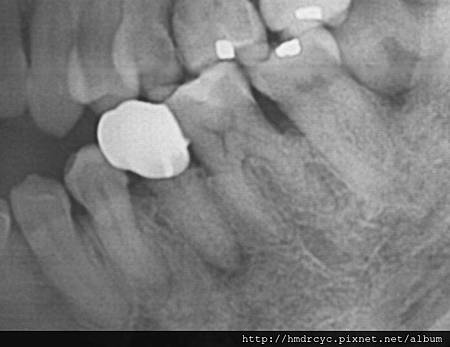

假牙必須利用X光片來更精確的判斷有沒有問題

在X光上面假牙是白色的影像

但X光片判讀困難 所以這部分必須仰賴醫師的專業

通常假牙底下牙齒會有幾個問題

比較難從外部檢查 而建議做X光片檢查

包括: